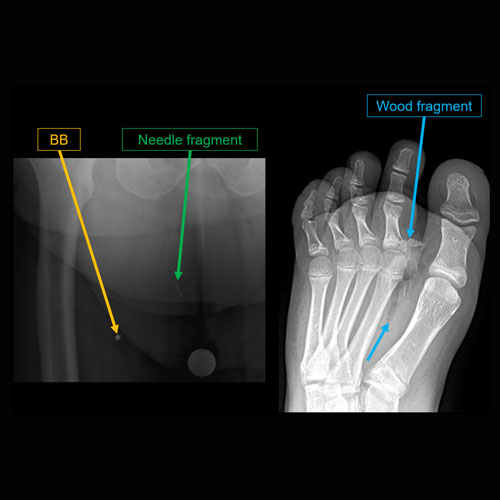

Section 1 Submit Findings CB1119 Findings Findings There are limitations. Yes No There is soft tissue reticulation, fullness, or obscuration of normal fat planes. Yes No There is soft tissue ulceration. Yes No There is soft tissue gas. Yes No There is a foreign body. Yes No There are fractures. Yes No There is periosteal reaction or osseous destruction suggesting osteomyelitis. Yes No There is cloaca, sequestrum, or involucrum. Yes No There is a joint effusion. Yes No There is periarticular osteopenia or erosions to suggest septic arthritis. Yes No There is malalignment, degenerative changes, or other gross internal derangement of the visualized joints. Yes No